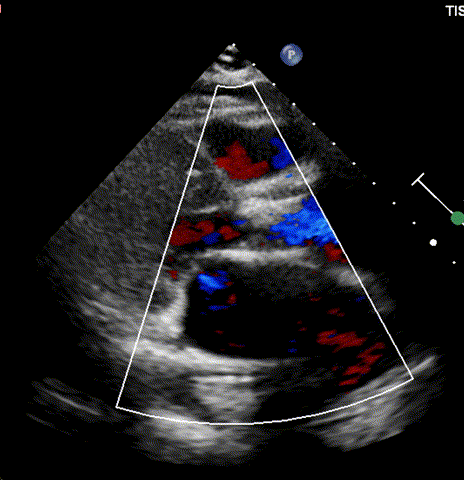

超声评估

通过术前精准评估,患者在全麻下行TAVR手术,DSA和食道超声双重引导,通过右侧股动脉建立工作路径,沿加硬导丝送入19mm*40mm球囊预扩张主动脉瓣,预扩张过程患者生命体征平稳,退出预扩张球囊后,利用可调弯输送器送入21# RENATUS瓣膜至升主动脉,猪尾巴导管再次造影确认位置。将21# RENATUS瓣膜顺利跨瓣,精准定位,精确释放,退出输送系统再次行主动脉根部造影,示瓣膜膨胀充分,无瓣口反流,无瓣周漏,冠脉血流正常,再次测主动脉根部压力及左心室压力,术后即刻平均跨瓣压差降至5mmHg,超声示术后峰值流速降至1.75m/s。瓣膜释放位置理想、形态及功能良好,瓣叶启闭良好,无外周血管损伤。

超声诊断为左房增大,室间隔增厚,升主动脉增宽;主动脉瓣功能性二叶瓣(Type1型)并退行性变,主动脉瓣重度狭窄;二、三尖瓣少量反流、肺动脉压稍高;左室舒张功能下降。